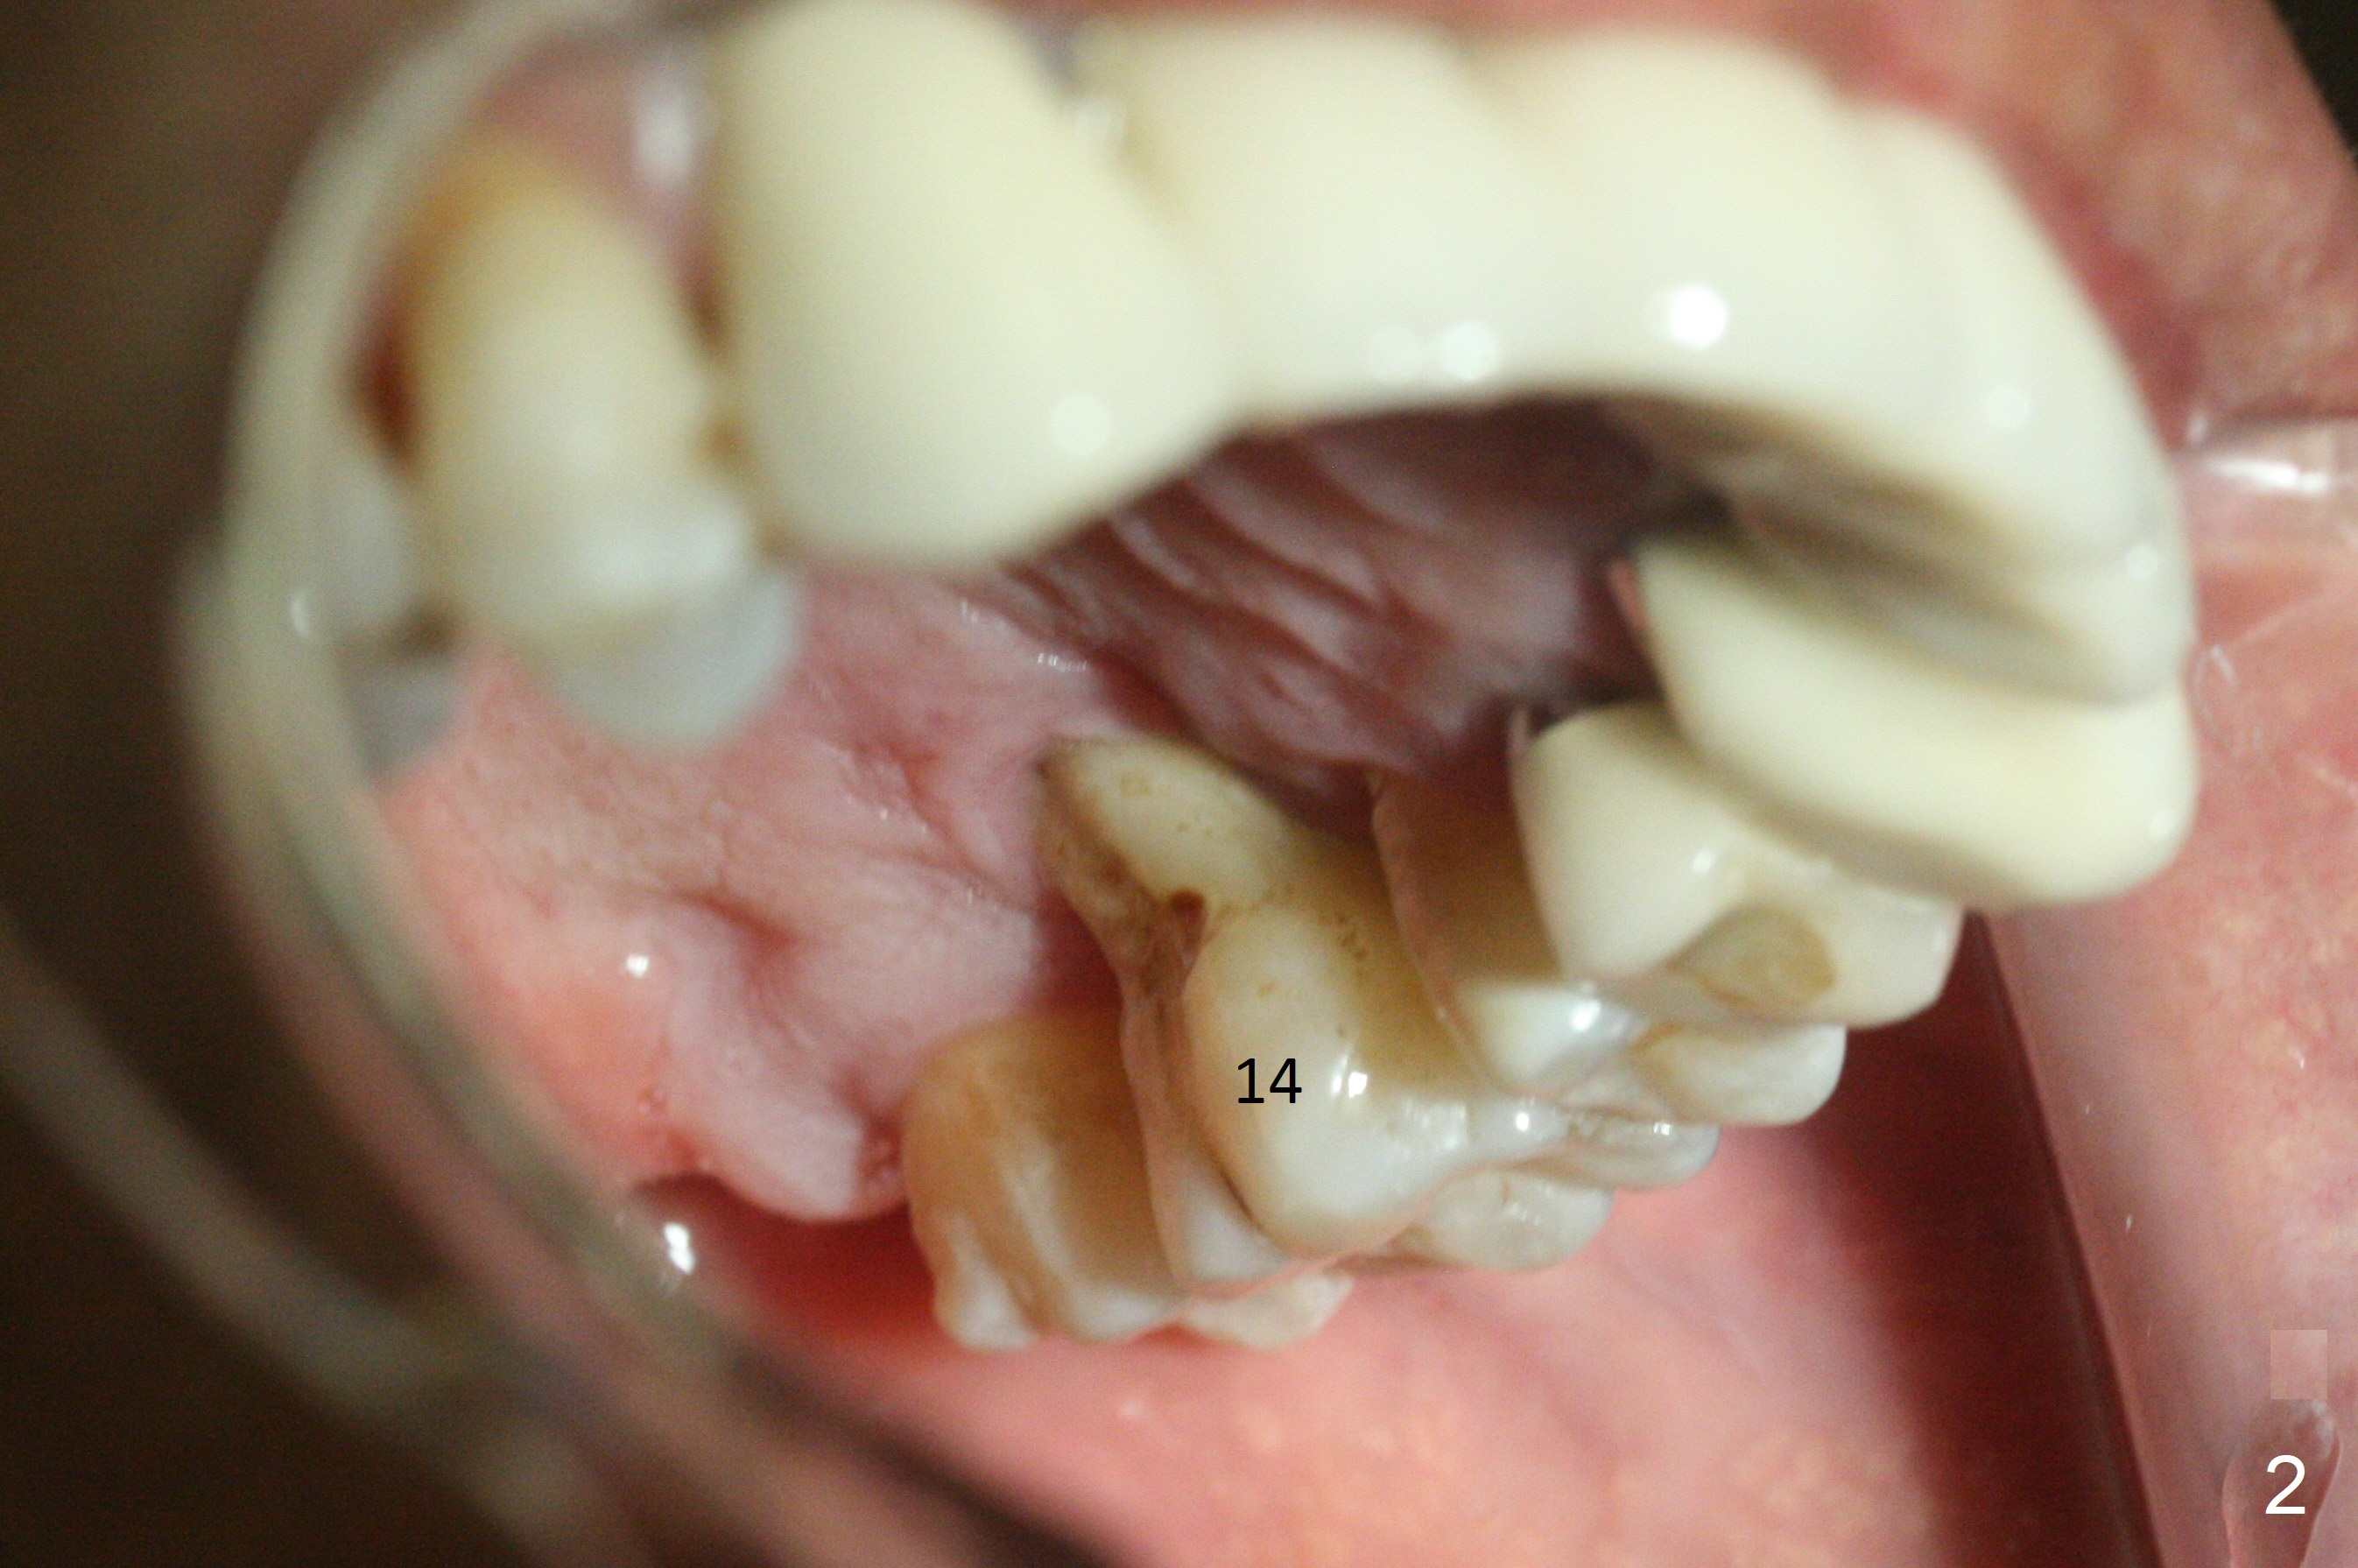

Abutment with 6 mm Cuff A 48-year-old man has mobile, symptomatic upper left 1st molar with severe gingival recession (Fig.1,2, particularly palatal). There appears no sinus floor. The thick gingiva (6 mm (Fig.3 pink)) will dictate a particular implant system. The long clinical crown suggests a long abutment (blue, 7 mm). After extraction and Clindamycin, use the smallest tap drill to initiate osteotomy until stability and sinus lift are achieved. PRF plug (1) and membrane (3) are to be prepared. Return to